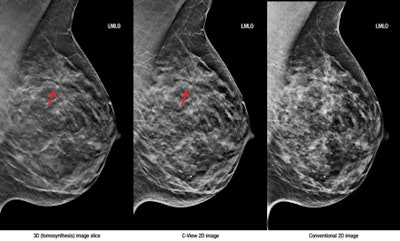

Left, 3D tomosynthesis image slice; middle, C-View 2D image; right, conventional 2D image. Images courtesy of Hologic."Large-scale clinical studies have shown that screening with Hologic's 3D mammography technology allows radiologists to visualize the breast in greater detail than with 2D mammography alone, which results in earlier detection of cancers while at the same time reducing the false positives associated with conventional 2D mammography that cause unnecessary anxiety and cost," the company said in a statement.

C-View 2D images may now be used in place of the conventional 2D exposure previously required as part of a Hologic breast tomosynthesis screening exam, according to the firm.

The software generates 2D images from the 3D data acquired during a breast tomosynthesis exam, eliminating the need for additional 2D exposures and, therefore, reducing radiation dose and exam time, Hologic said.